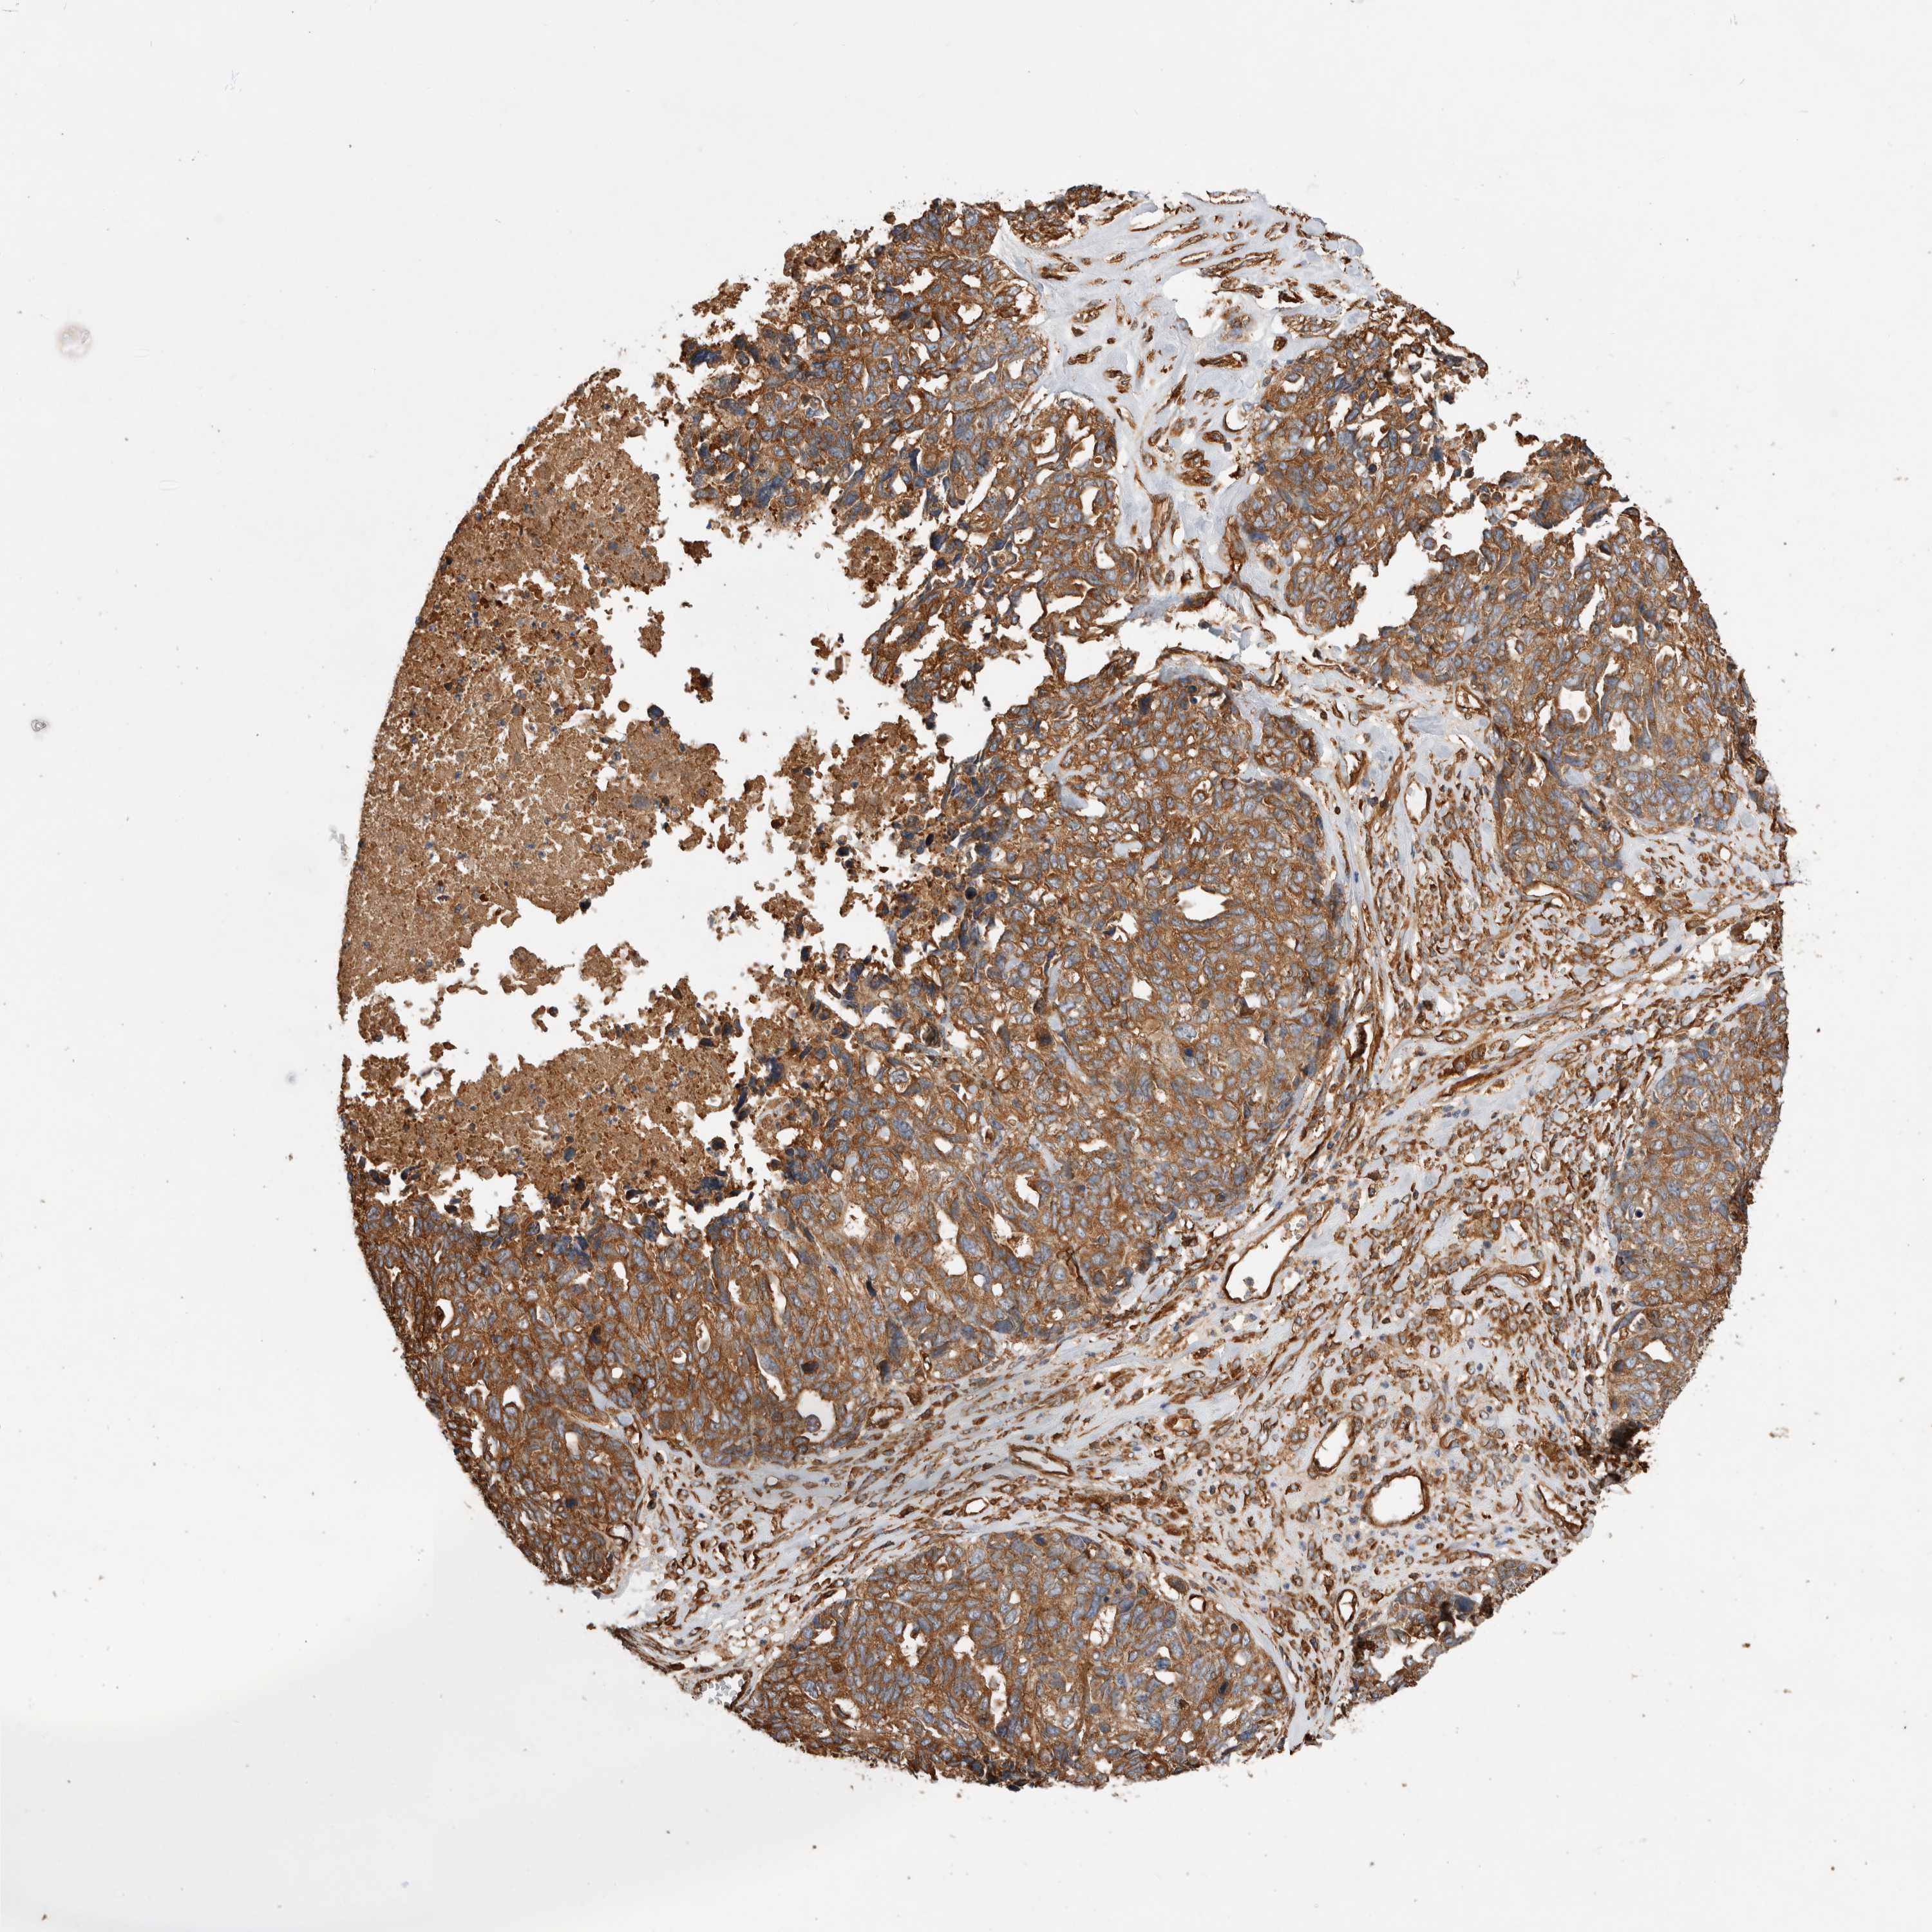

OVARIAN CANCER - Protein expressioni

A mouse-over function shows sample information and annotation data. Click on an image to view it in a full screen mode. Samples can be filtered based on level of antibody staining by selecting one or several of the following categories: high, medium, low and not detected. The assay and annotation is described here.

Note that samples used for immunohistochemistry by the Human Protein Atlas do not correspond to samples in the TCGA dataset.

Antibody stainingi

Antibody staining in the annotated cell types in the current human tissue is reported as not detected, low, medium, or high, based on conventional immunohistochemistry profiling in selected tissues. This score is based on the combination of the staining intensity and fraction of stained cells.

Each image is clickable and will lead to virtual microscopy that enables deeper exploration of all samples and also displays staining intensity scores, fraction scores and subcellular localization as well as patient and tissue information for each sample.

Antibody HPA026087

Staining

High

Medium

Low

Not detected

Intensity

Strong

Moderate

Weak

Negative

Quantity

>75%

75%-25%

<25%

None

Location

Nuclear

Cytoplasmic/membranous

Cytoplasmic/membranous,nuclear

Cystadenocarcinoma, serous, NOS

Carcinoma, endometroid

Cystadenocarcinoma, mucinous, NOS

Carcinoma, NOS